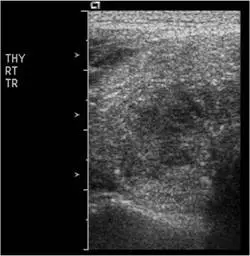

⼀位女性病患右側甲 狀腺及右下邊脖⼦淋巴腺無痛性腫⼤,其右側甲狀腺灰階及彩⾊杜⼘勒超⾳波檢查如圖,最可能的診斷 為何?

本題考慮一位女性病患出現右側甲狀腺及右下頸部淋巴結無痛性腫大,提供右側甲狀腺的灰階(B-mode)及彩色杜卜勒(color Doppler)超音波影像,要求判斷最可能的診斷。無痛性甲狀腺腫塊合併頸部淋巴結腫大,配合超音波影像特徵,是甲狀腺乳突狀癌(papillary thyroid carcinoma, PTC)的典型臨床表現。

本題共提供三張超音波影像(THY RT TR/SAG 標示,即右側甲狀腺横切及縱切面):

影像二(B-mode 縱切面):

- 縱切面顯示結節呈不規則形態,縱橫比(taller-than-wide shape)傾向,邊緣可見**微